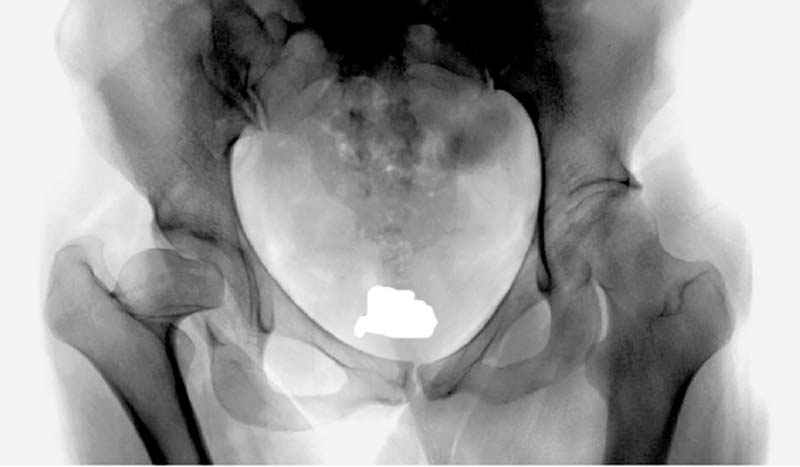

Рис.1 Трехмерная модель тазобедренного сустава с аналогом связки головки бедра. Заметно, что из торца головки выходит капроновый шнур, который с одной стороны прикрепляется к ножке бедренной части модели, а другой его конец, проходя через головку и прикрепляется к вертлужной части модели. Динамометр оказывается не нагруженным, так как аналог связки головки бедра замыкает подвижный узел модели во фронтальной плоскости.

Рис.2 Та же трехмерная модель тазобедренного сустава без аналога связки головки бедра. Пружина динамометра удерживает тазовую часть модели от опрокидывания, поддерживая стабильность так же, как отводящие мышцы обеспечивают ее в отсутствии связки головки бедра.